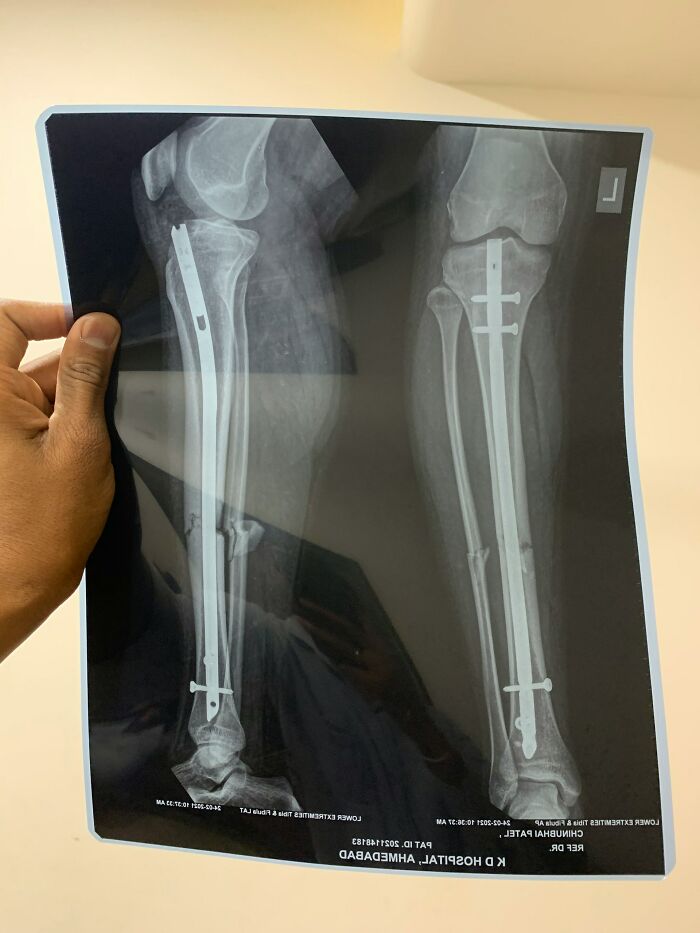

I work as a statistician in a major hospital so I see and catalogue A LOT of weird things.

Worst thing id seen was someone come in complaining of leg pain and showing signs of septic shock. After examination dr orders scans and theres 2 metal rods (one in each leg) that weren't on their file. Turns out the patient has been to SE Asia to get a height altering surgery and the 'dr' had used items youd pick up from the local hardware store to fix the bones after breaking.

After extensive surgery patient lost the lower part of one leg and was lucky to keep the 2nd.

There’s patient information (name, ID) on that x-ray. Hope it’s fake.